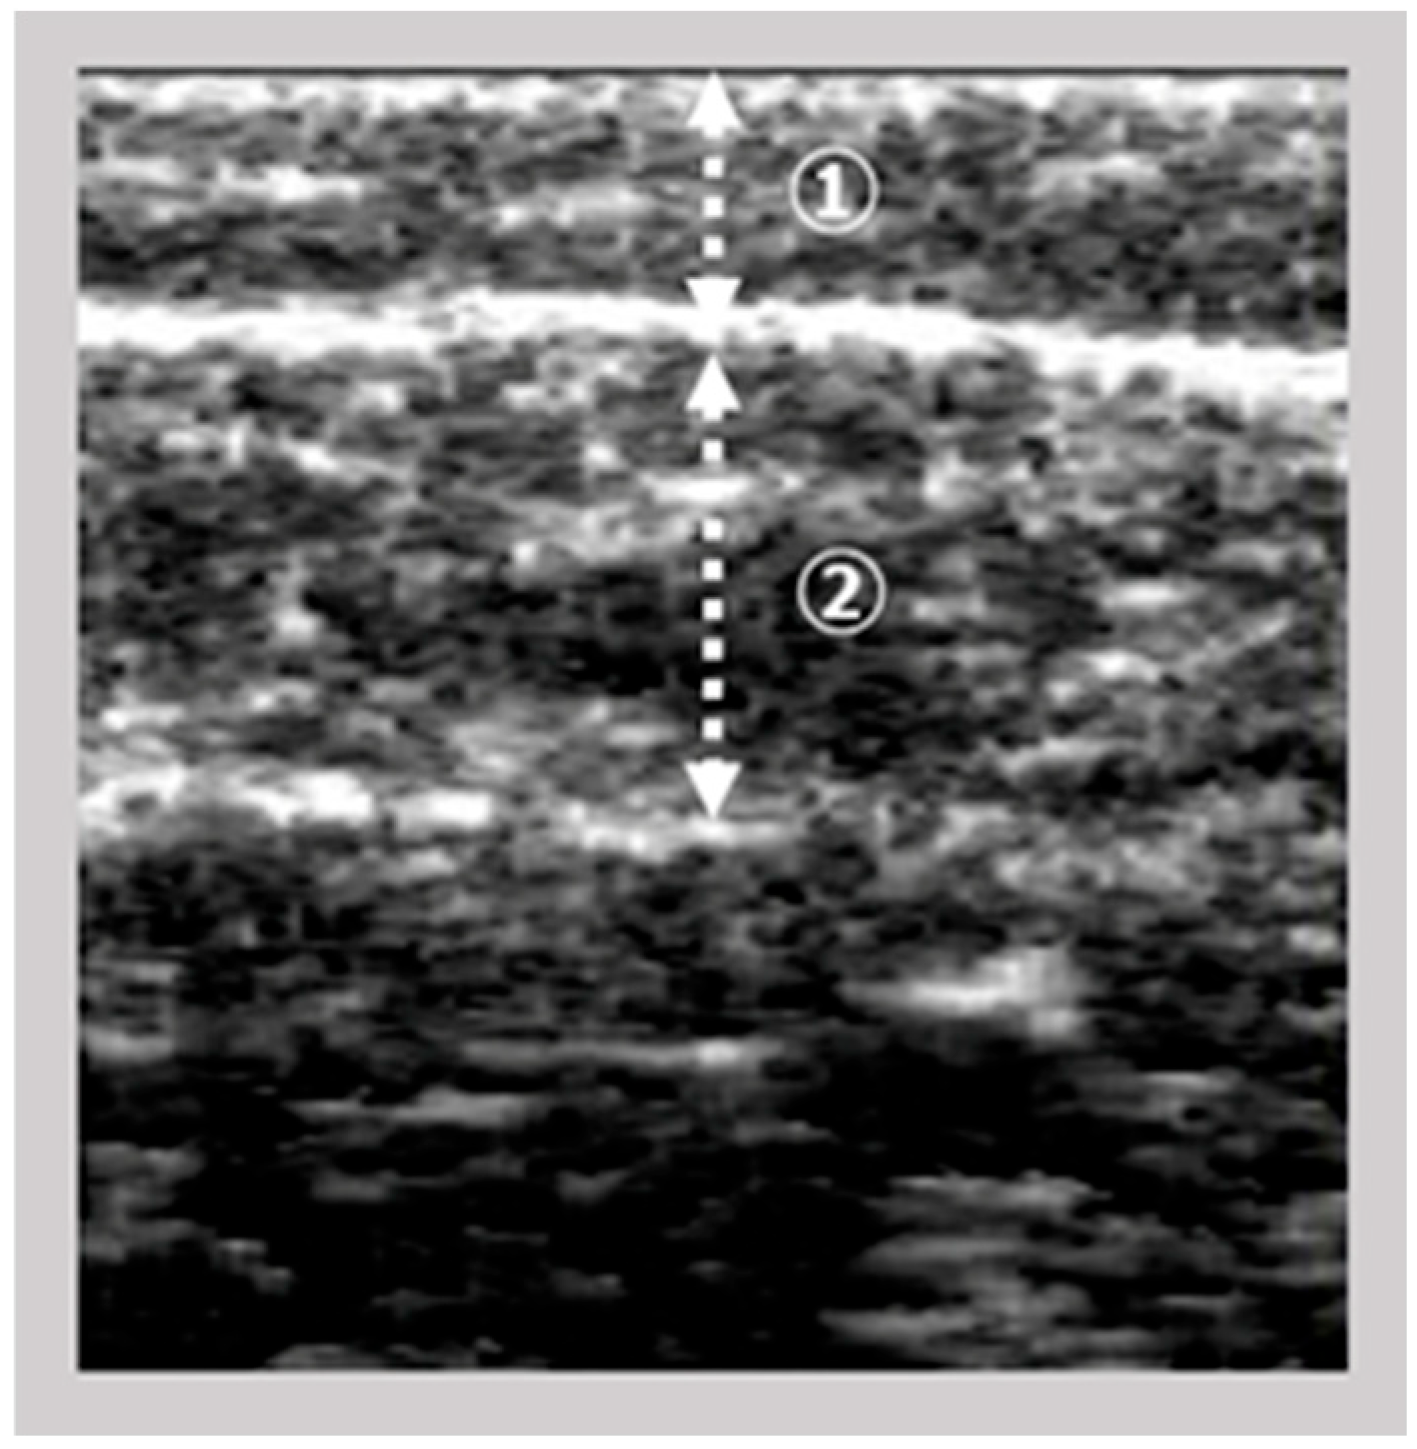

The images of the gastrocnemius muscle were obtained using an ultrasound device (View’s i; SAKAI Medical Science Co., Ltd., Tokyo, Japan) equipped with a 6-MHz linear array probe. In all patients, ultrasonography measurements were performed under fixed settings, including B-mode, a fixed dB dynamic range, fixed gain, and fixed depth of focus, which were preconfigured for skeletal muscle imaging and intentionally made non-modifiable by the manufacturer. The mode settings are not disclosed due to the device’s patent protection. The participants were assessed in a seated position with both knees flexed at 90° and the ankles at 0°. The examiner vertically and gently positioned the probe on the right medial gastrocnemius at the point of maximum below-knee circumference. The A-mode display on the device was monitored simultaneously. The examiner captured images of the subcutaneous adipose tissue and gastrocnemius muscle (Figure 1). The subcutaneous fat thickness (SFT) was defined as the distance between the skin surface and the upper fascia of the gastrocnemius. Meanwhile, the GT was defined as the distance between the subcutaneous fascia and the deep fascia. A previous study investigated the intra-rater reliability of GT measurements in healthy adults when the probe pressure was maintained below 100 gf [9] reported decreased reliability under this condition. Based on these results, we set the probe pressure at 200 gf in this study to minimize measurement error.

Ultrasound images were exported as Joint Photographic Experts Group (JPEG) files, and the EI of the gastrocnemius muscle was calculated using Adobe Photoshop Elements (Adobe Systems, Inc., San Jose, CA, USA). The target area was selected to include as much muscle tissue as possible while avoiding the surrounding fascia. The selected area was converted to an 8-bit grayscale image, with the mean image brightness presented as a value ranging from 0 (black) to 255 (white) (Figure 2). The EI was calculated as the mean image brightness [10]. This study analyzed the EI and GT of the leg with the lower ABI.

Figure 1. Ultrasonographic image of the gastrocnemius muscle; ① subcutaneous fat thickness; ② gastrocnemius thickness (GT).